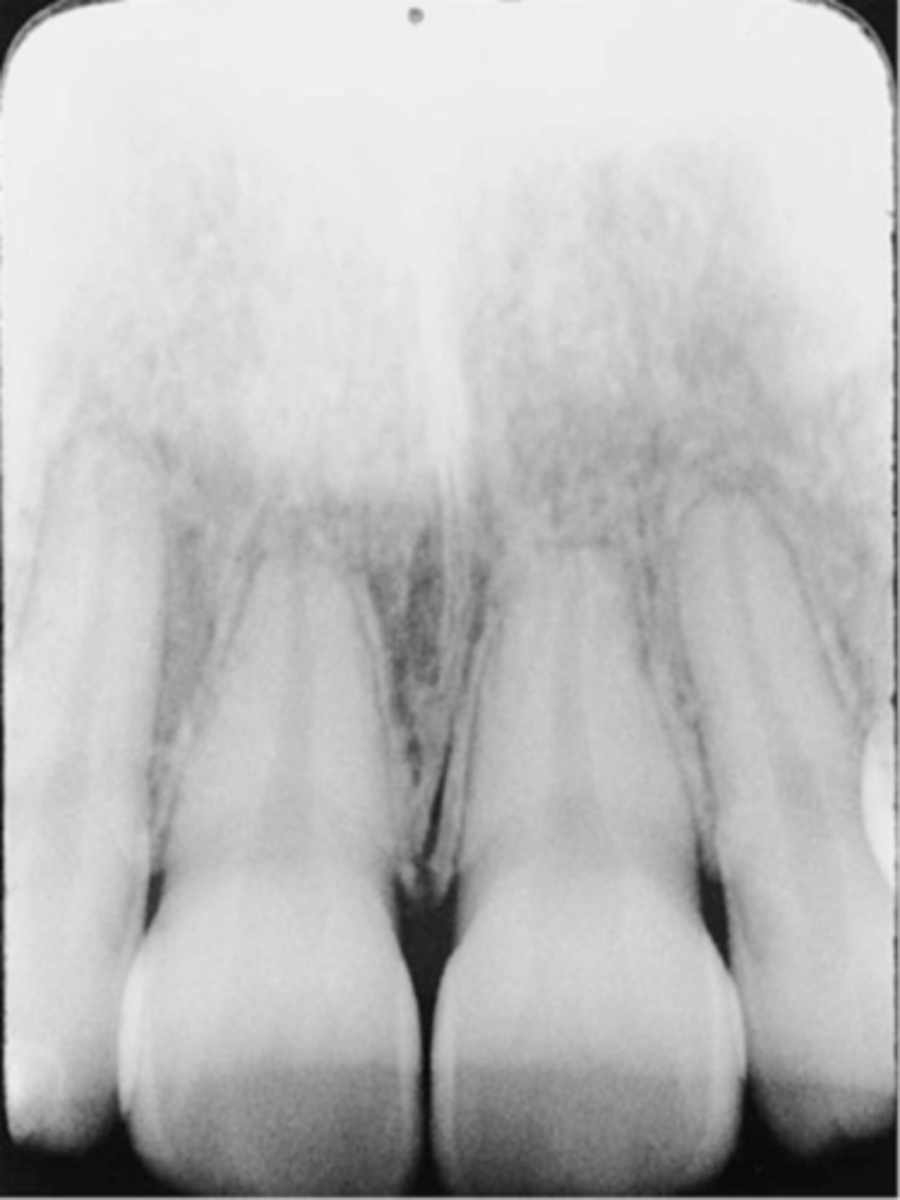

Incorrect Vertical Angulation-->Foreshortened Images

-Teeth appear short with blunted roots

-Vertical angulation was excessive, or too steep, resulting in images that are shorter than the actual teeth

-This occurs more often with the bisecting technique

-To prevent do not use excessive vertical angulation

Tube Head & PID-->Foreshortening of the image

-Excessive angulation (too steep) causing shortening of the anatomy of the teeth and/or cutting off occlusal or incisal edge.

1. PID Too steep Vertical angulation

2. Foreshortening of the image: Excessive angulation (Too Steep)

Foreshortened image; Vertical angulation is too steep, Possible deflected film.